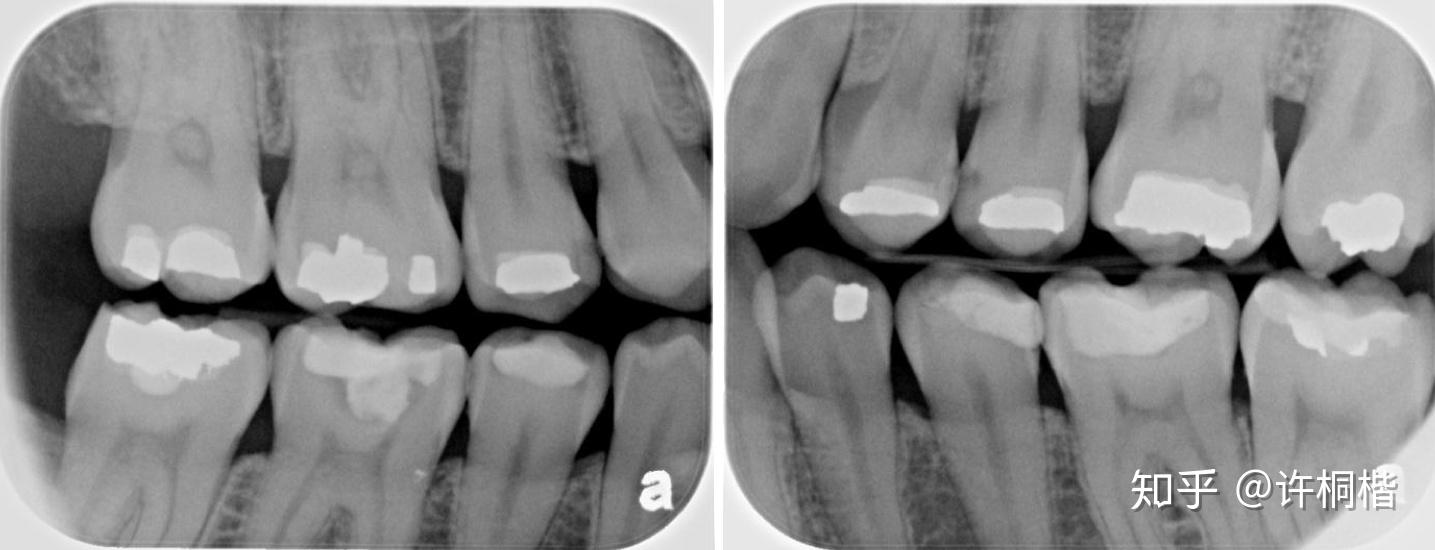

如何发现成人邻面牙齿早期龋坏

图片尺寸1435x550

邻面龋

图片尺寸680x510